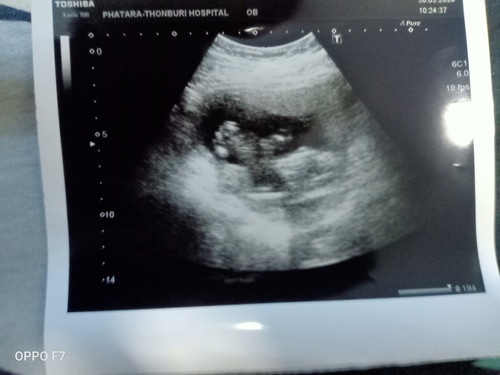

ตอนนี้ 14w ยังแพ้ยุ น้ำหนักลงกินข้าวไม่ค่อยได้ เบื่ออาหาร ร้องไห้ง่าย แถมชอบกินของหวานมาก ดูช่วยว่าอาการแบบนี้จะเป็นผู้ชาย หรือ ผู้หญิงค่ะ ?